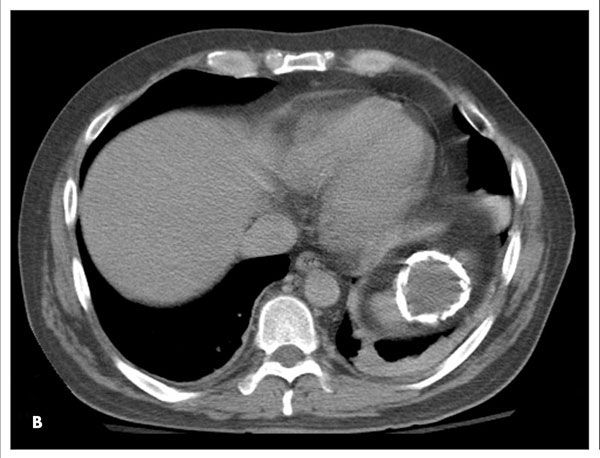

A 38-year-old man found lying on the floor in his home was hospitalized because of alcohol intoxication. A chest radiograph showed a large calcified lesion in the left upper abdomen (A). A CT scan with intravenous contrast revealed a large, well-defined, cystic mass with mural calcification in the spleen (B). The CT findings were not consistent with a vascular malformation or echinococcal cyst-specifically, the mass was sharply demarcated, unilocular without septations, and round with a thin wall and attenuation similar to water. Urine Histoplasma antigen test results were negative.

The patient underwent CT-guided aspiration of the cyst, and the fluid was cultured and examined under microscopy. Culture, cytology, and Gram stain results were negative, and no parasitic elements were identified under microscopy. Based on these results and the lack of a patient history of pancreatitis, traumatic calcified splenic cyst was diagnosed.

Calcified splenic cysts most often occur in patients who are prone to recurrent blunt abdominal trauma, such as alcoholics. However, this is a diagnosis of exclusion; more common, treatable causes of splenic masses need to be ruled out first.